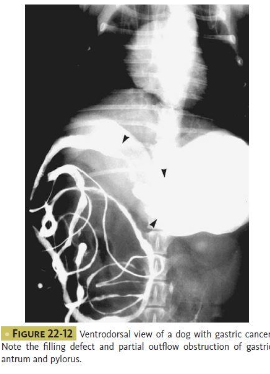

Overall gastric tumors are __ with __% of maligancies.

rare, <1%

Dogs tend to get what type of gastric tumors?

adenocarcinoma (70-80%)

smooth muscle tumors, GIST, lymphoma, others

Cats tend to get what type of gastric tumors?

lymphoma - solitary or component of higher stage dz

adenocarcinoma is rare

What are the risk factors for gastric tumors (adenocarcinoma) in dogs?

breed - Belgian shepherds, rough coated collies

male sex 2.5:1 M to F ratio

What are the risk factors for gastric tumors (lymphoma) in cats?

chronic gastritis

H. pylori infection

What clinical signs are seen with gastric tumors?

vomiting, anorexia, weight loss, anemia

signs may be prolonged

How are gastric tumors diagnosed?

imaging: radiographs ± contrast, ultrasound, CT

biopsies and histopathology: endoscopy, sx